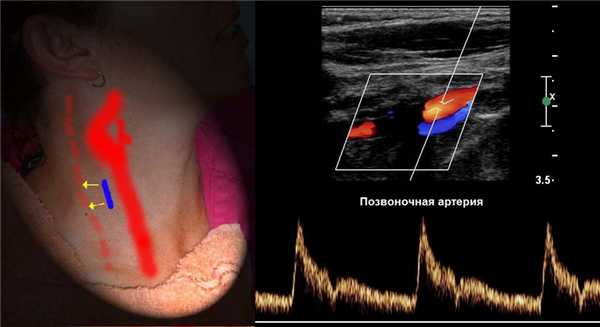

ПА отходит от I сегмента ПКА, поднимается через отверстия поперечных отростков С6-С1, через большое затылочное отверстие входит в череп.

I сегмент от устья до С6; II сегмент в канале поперечных отростков С6-С2; III сегмент от С2 до входа в череп; IV сегмент до слияния в основную артерию.

ПА сканируют продольно кнутри от кивательной мышцы, от угла нижней челюсти до верхнего края ключицы.

Для ПА характерна асимметрия, обычно левая больше правой. Когда ПА менее 2 мм, можно говорить о гипоплазии.

Для исследования I сегмента ПА датчик смещают до ключицы. В норме ПА отходит от ПКА на уровне С7 и входит в костный канал на уровне С6.

II сегмент ПА имеет прерывистый вид, т.к. проходит в костном канале поперечных отростков С6-С2 и на месте поперечных отростков акустическое затенение.

Если на смежных участках скорость кровотока примерно одинаковая, значит патологических изменений в «слепой» зоне нет.

Спектр II сегмента ПА по форме похож на ВСА, Vps и Ved в 1,5 раза ниже, поток исключительно антеградный. Vps может снижаться на верхних отрезках, но не более 20%.